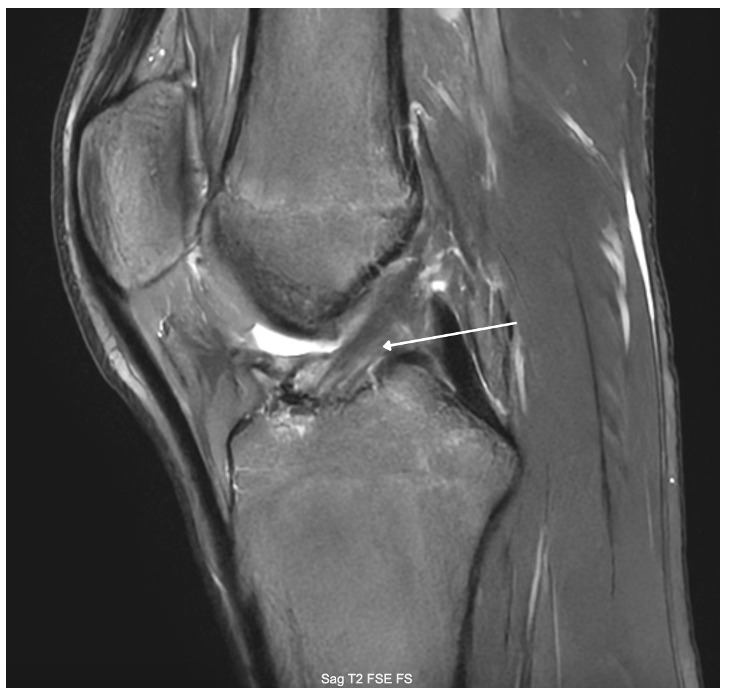

At the 6-month-follow-up, the patient reported no pain at the surgical sites and had regained full range of motion and strength of the hamstring and quadriceps (5/5). He also had a full range of motion. At 7-month-post surgery, an MRI was obtained to evaluate graft maturation prior to return to sport. The scan demonstrated an intact ACL with a robust graft, consisting of biologic healing (Figure 3). The patient was advised to continue aggressive strengthening over the next 4 weeks in anticipation of the upcoming football season. He was cleared for return to sport at approximately 8 months postoperatively. At the 1-year follow-up, the patient has done exceptionally well with no significant issues or complaints and was able to complete his football season, and was preparing for basketball season. He then revisited 18 months postoperatively where he demonstrated full knee flexion and extension (Figure 4a-b) and received the Lysholm Knee Score (LKS), which increased from 67/100 to 100/100, and a Knee Injury and Osteoarthritis Outcome Score (KOOS) with a base of 61/100, which increased to 94/100.